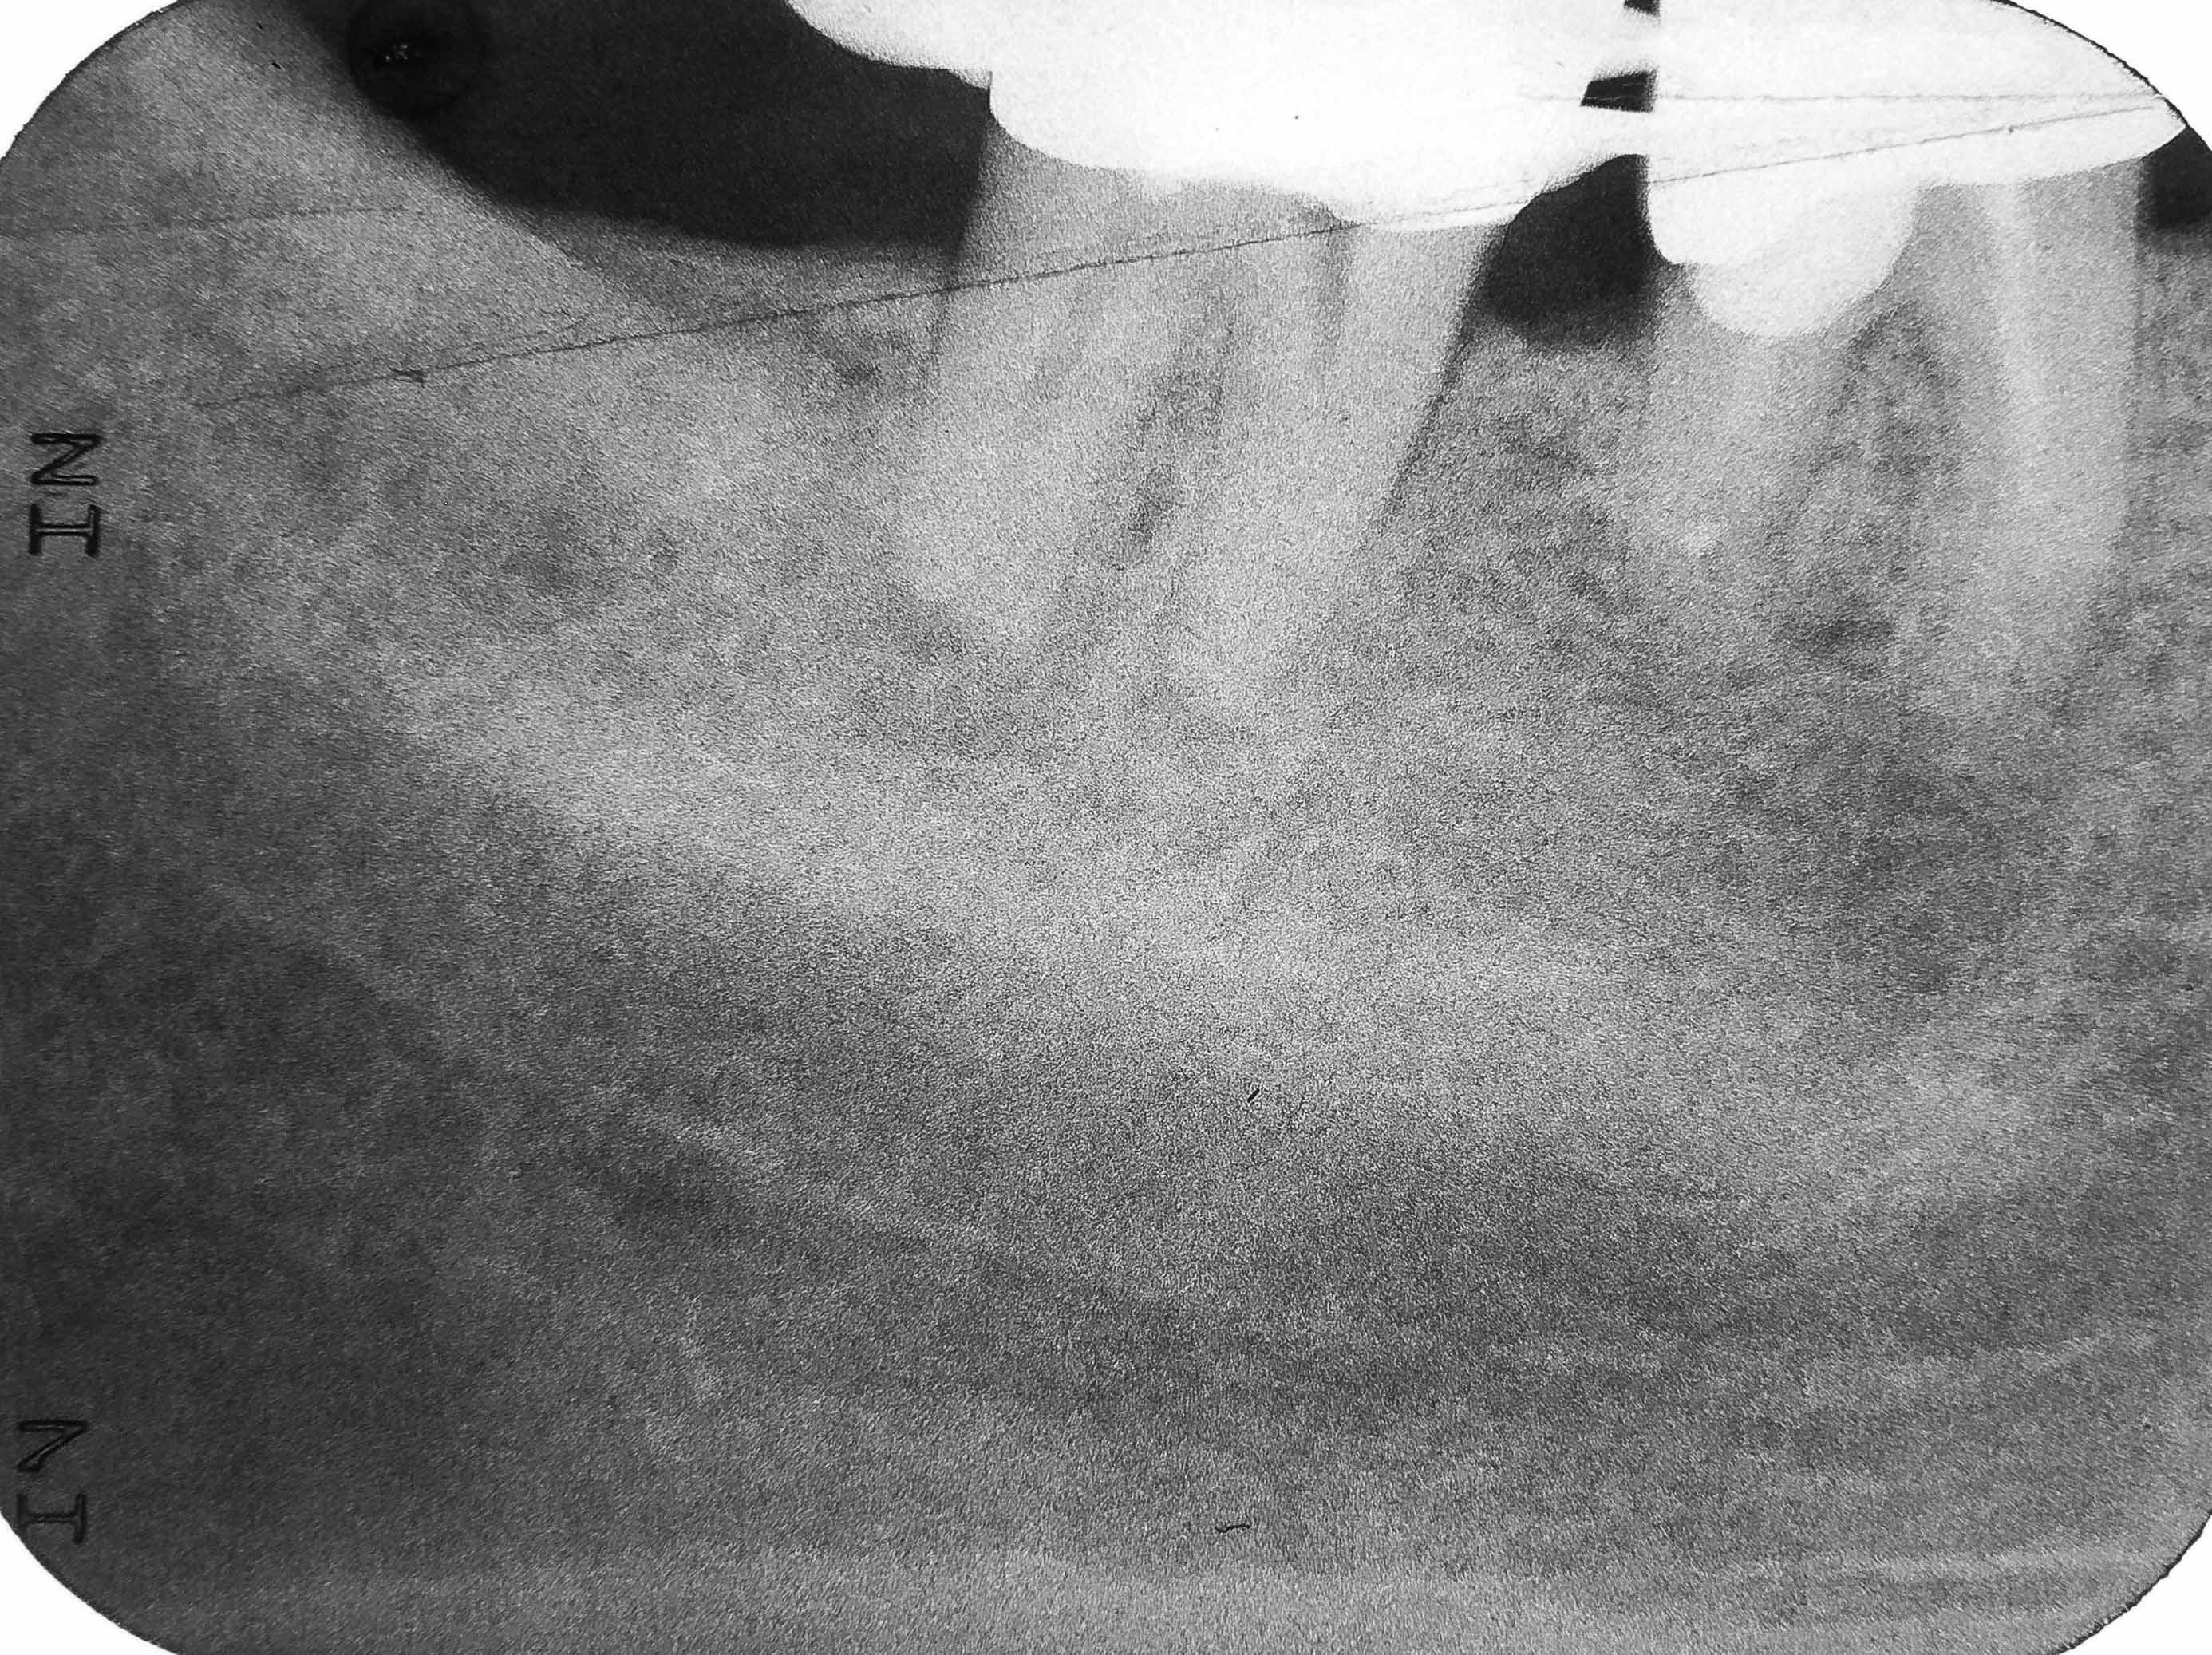

SANYO DIGITAL CAMERA

2772 × 2074

Silberstift Zwei

Stift entfernt